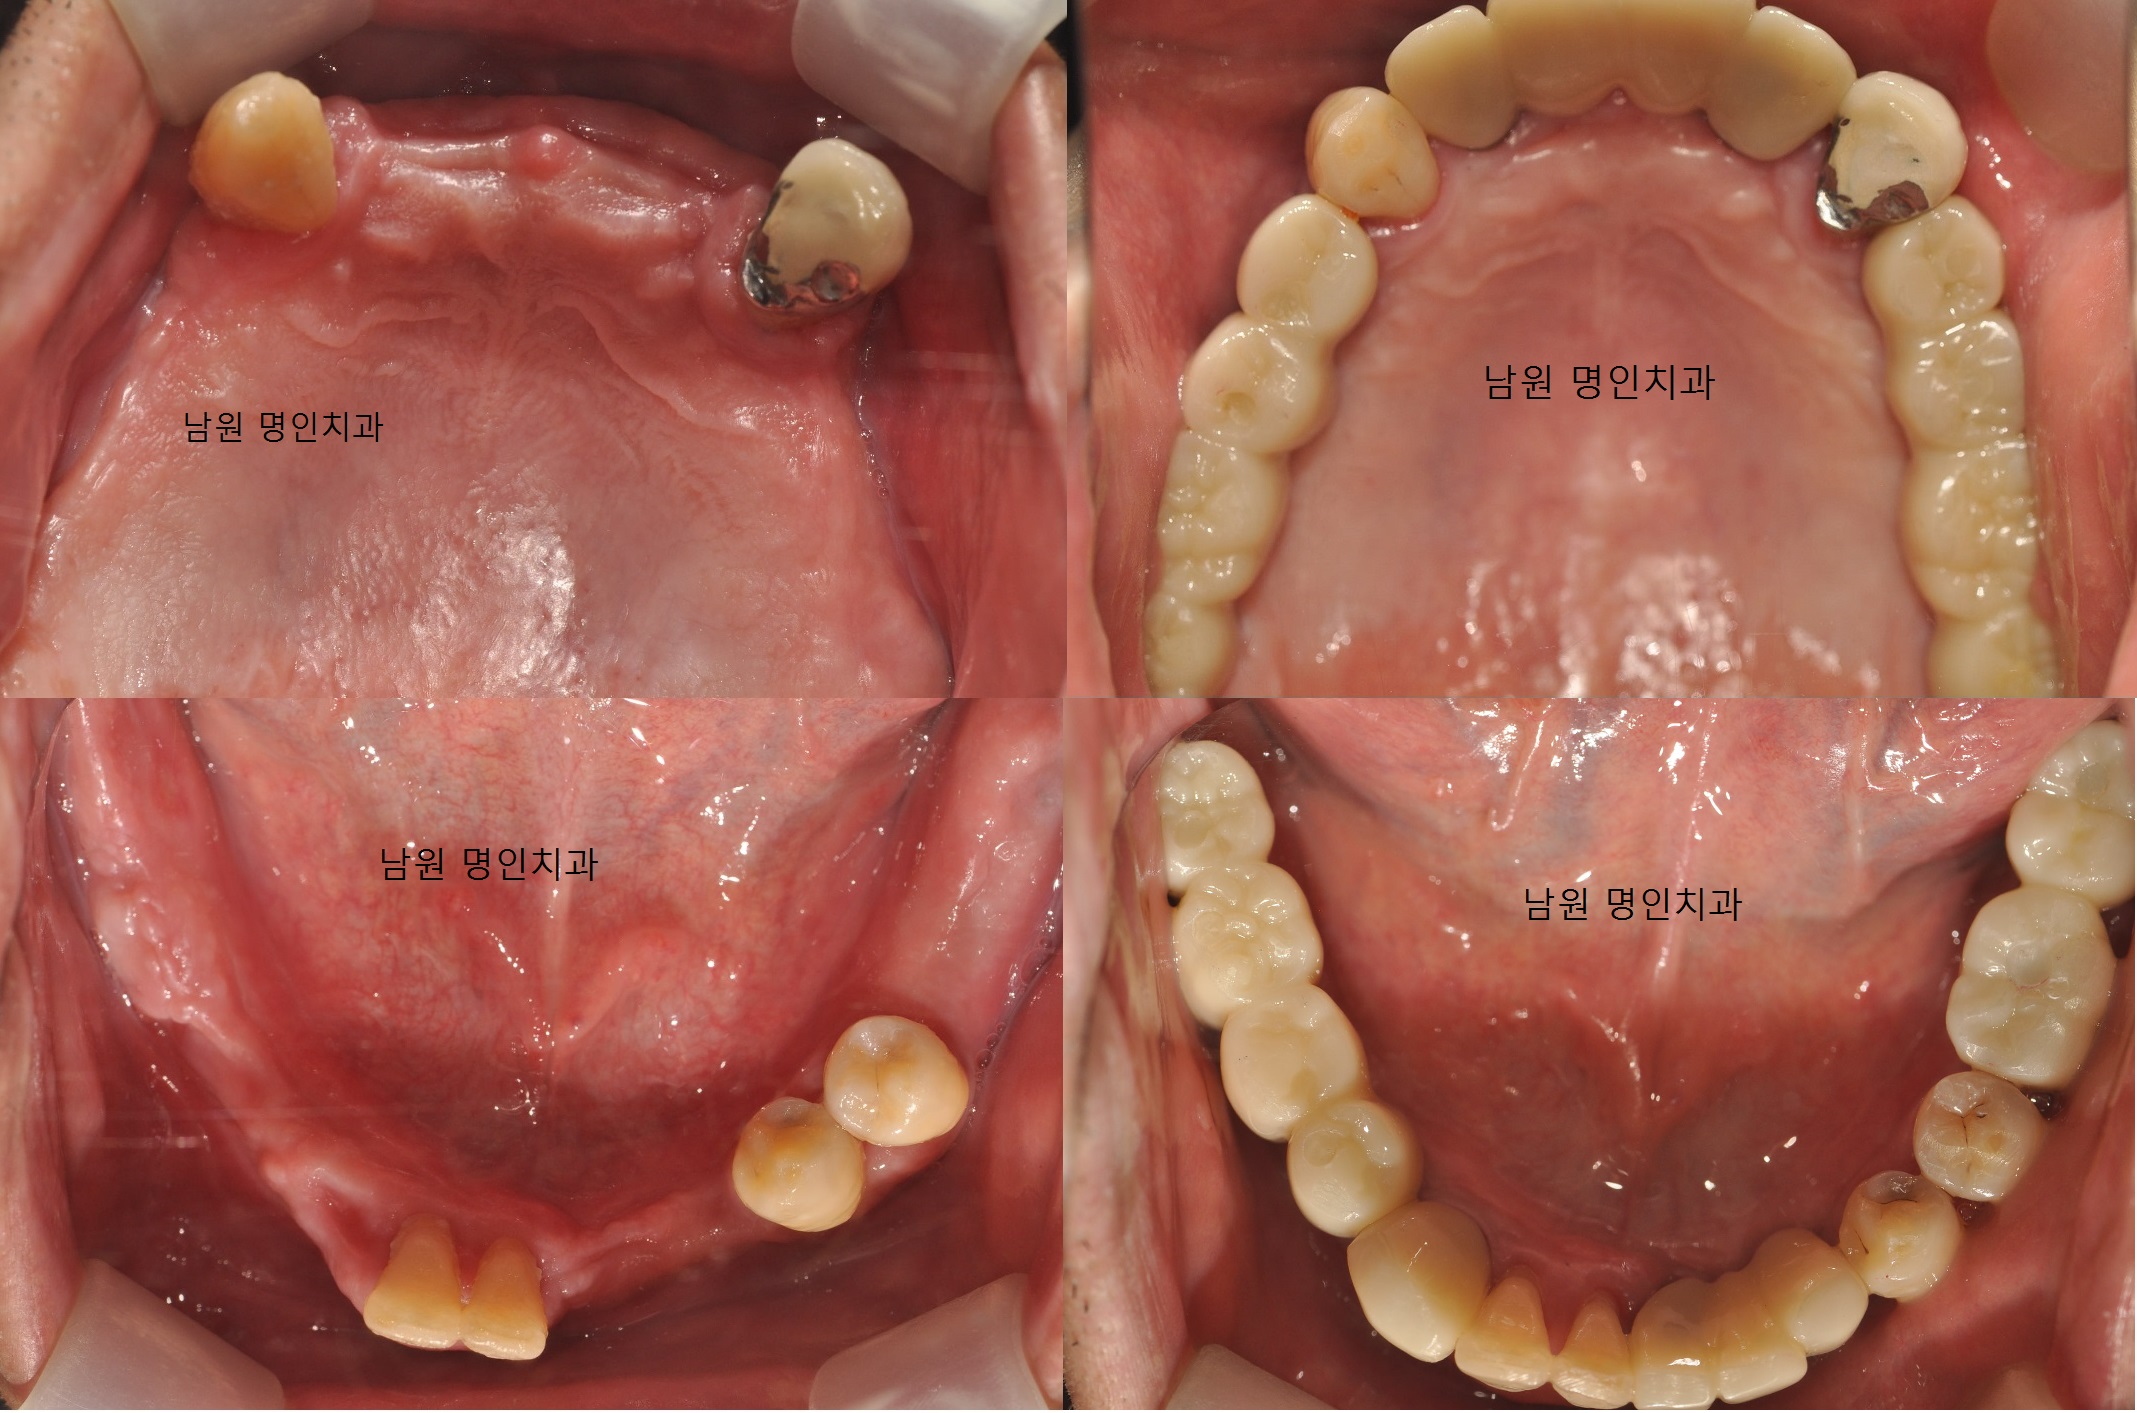

명인치과의원

여기는 남원 터미널 근처에 있어서 접근성이 정말 좋아요. 특히 임플란트를 전문으로 하는 곳이라 저도 임플란트 상담받으러 방문했었는데요, 원장님이 두 분 계셔서 각자 전문 분야를 맡아 책임 진료를 해주신다고 해요. 임플란트 1만례를 달성했다고 하니 괜히 더 믿음이 가더라고요.

저처럼 임플란트나 고난이도 진료가 필요한 분들에게 정말 좋은 선택지가 될 것 같아요. 상담받을 때부터 전문가의 느낌이 확 와닿았습니다.

초진이라 긴장했는데, 직원분들도 의사선생님도 정말 친절하셔서 좋았어요. 치아 상태에 대해 상세히 설명해주시고 진료도 빠르고 안 아프게 봐주셔서 다음에 또 오고 싶어요!

4.9 / 5